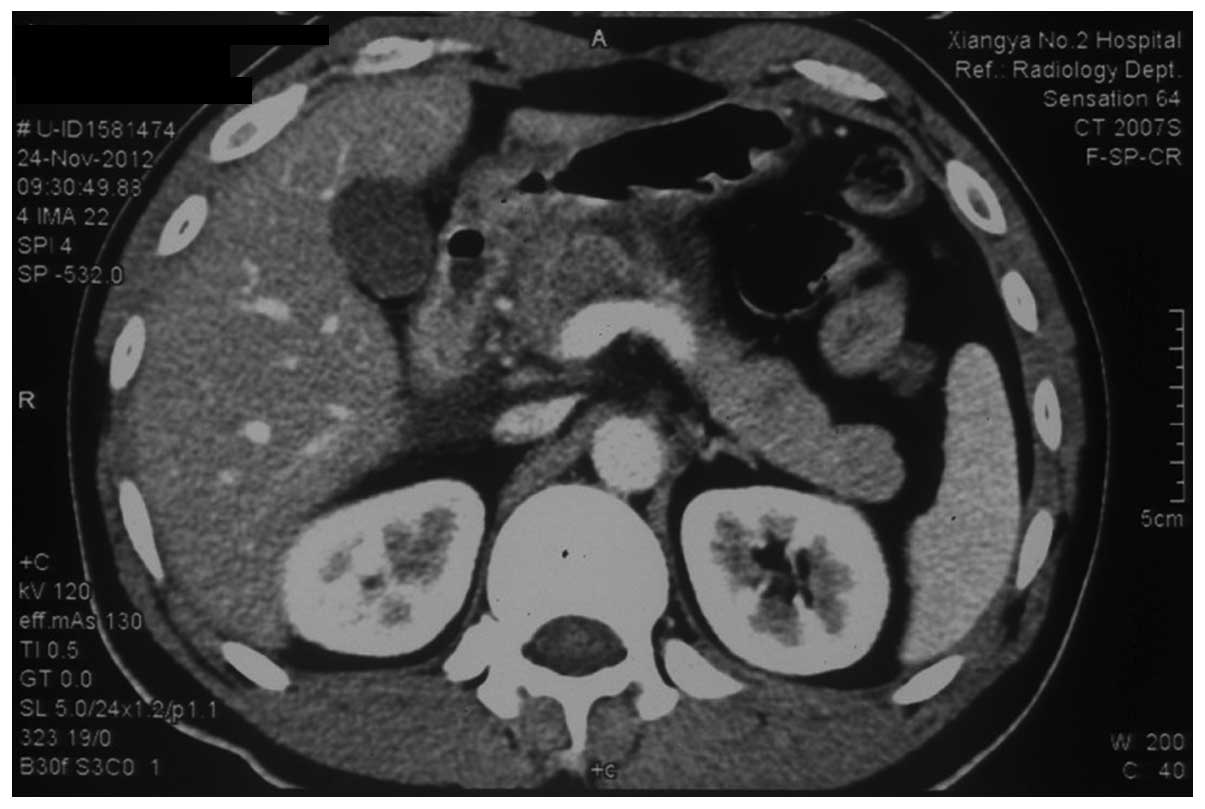

A 29-year-old Chinese male was admitted to The Second Xiangya Hospital of Central South University (Changsha, China) due to ENKTL in October 2012. The patient’s medical history included the chronic hepatitis B virus (HBV) infection and a right front-parietal lobe transitional meningioma resection, which was conducted in June 2010. A physical examination was performed at the time of admission and the patient exhibited the following: Height, 173 cm; weight, 72 kg; and body surface area, 1.86 m2. The results of the biochemical analysis were within the normal limits with the exception of increased HBV-DNA copies (3.61×107 IU/ml). In addition, an abdominal contrast-enhanced computed tomography (CT) scan showed no evidence of an abnormal pancreas, spleen or kidneys, however, fatty liver was observed. Combination chemotherapy was performed to treat the patient, which included intravenous injections of L-Asp (6000 IU/m2) for seven continuous days, 1000 mg/m2 gemcitabine on days one and eight and 85 mg/m2 oxaliplatin on day one. Additionally, the patient was administered with 0.1 g lamivudine per day as an antiviral treatment. Acute and severe epigastric pain occurred two days after completion of the chemotherapy and a physical examination revealed epigastric tenderness. The values of total bilirubin (44.4 μmol/l) and direct bilirubin (9.7 μmol/l) increased, serum amylase (964.2 μl), urinary amylase (219.7 μl) and fasting glucose (8.11 mmol/l) were significantly increased and the level of serum calcium (1.86 mmol/l) was markedly decreased, which indicated severe inflammation and dysfunction of the pancreas. The patient immediately received resuscitation fluid intravenously and a supplement of electrolytes. Meperidine and somatostatin were administered to relieve the pain, and to decrease the secretion of pancreatic fluid and total parenteral nutrition, respectively. A contrast-enhanced CT scan of the abdomen (Fig. 1) revealed diffuse swelling of the pancreas and peripancreatic fluid exudation, demonstrating acute pancreatitis. The patient presented with dizziness and exacerbation of abdominal pain on the subsequent night. A biochemical analysis of the serum demonstrated serum amylase, fasting glucose, calcium and serum triglyceride levels of 177.3 μl, 10.45, 0.57 and 3.85 mmol/l, respectively, indicating exacerbation of the pancreatic injury. On the next morning, the patient was thirsty and experienced heart palpitations. A physical examination identified tension in the abdominal muscles, epigastric tenderness, rebounding pain and the disappearance of gurgling sounds. The electrocardiogram identified a significantly higher heart rate with an undetectable blood pressure. The patient succumbed 72 h after completion of the chemotherapy.

Figure 1

Computed tomography scan demonstrating diffuse swelling of the pancreas and peripancreatic fluid exudation.